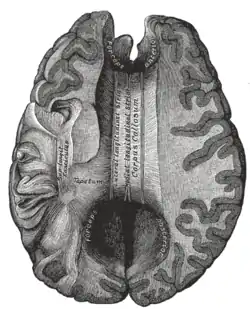

Мозолисте тіло (лат. corpus callosum) — широкий, плаский пучок нервових волокон довжиною близько 10 см під корою головного мозку у товщі поздовжньої щілини (лат. fissura longitudinalis). З'єднує ліву і праву півкулі головного мозку, забезпечує міжпівкульний зв'язок. Це найбільша структура білої речовини головного мозку, що складається з 200—250 млн контралатерально спрямованих (назустріч один одному, з обох сторін)аксонів кіркових нейронів.

Задня частина мозолистого тіла — валок (лат. splenium); передня називається коліном (лат. genu); між ними знаходиться стовбур мозолистого тіла. Частина між тілом і валком звужена й називається перешийком (лат. isthmus). Ростральна платівка — частина мозолистого тіла, що знаходиться дозаду й донизу від найбільш передньої частини коліна мозолистого тіла, як показано на сагітальному зображенні мозку праворуч. Кінцеву її частину називають дзьобом (за схожість із пташиним дзьобом).

Волокна по обидві сторони мозолистого тіла отримали назву променистості, оскільки променеподібно входять у білу речовину півкуль головного мозку й прямують до різних ділянок кори. Одні, згинаючись уперед від коліна, йдуть у лобову частку утворюють передні щипці, а другі, згинаючись назад у потиличній частці, утворюють задні щипці. Між цими двома частинами знаходиться основний стовбур мозолистого тіла, з якого волокна простягаються латерально в обидві сторони в скроневі частки, і покрівлю центральної частини бічного шлуночка[2][3].